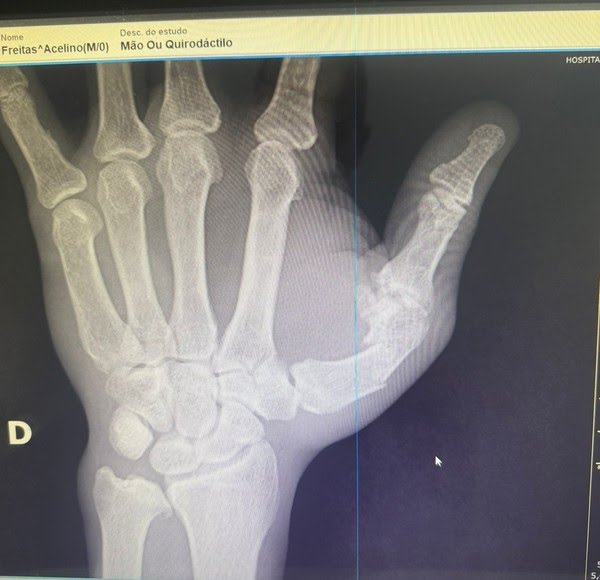

Popó quebrou a mão durante a confusão e a cirurgia deve durar cerca de duas horas e meia. O g1 teve acesso às imagens de raio-X e confirmou que a coisa é séria: o osso do polegar está quebrado e desviado. Os médicos explicaram que, sem cirurgia, as sequelas poderiam comprometer a carreira do boxeador.

Segundo os especialistas, o tratamento vai incluir placa, parafusos ou pinos, muita coisa chique e tecnológica. A boa notícia é que, depois da operação, Popó já poderá mexer a mão no dia seguinte, sem peso, e em cerca de seis semanas deve estar liberado para atividades de academia. Mas para voltar a dar socos profissionais, vai precisar esperar uns dois meses.